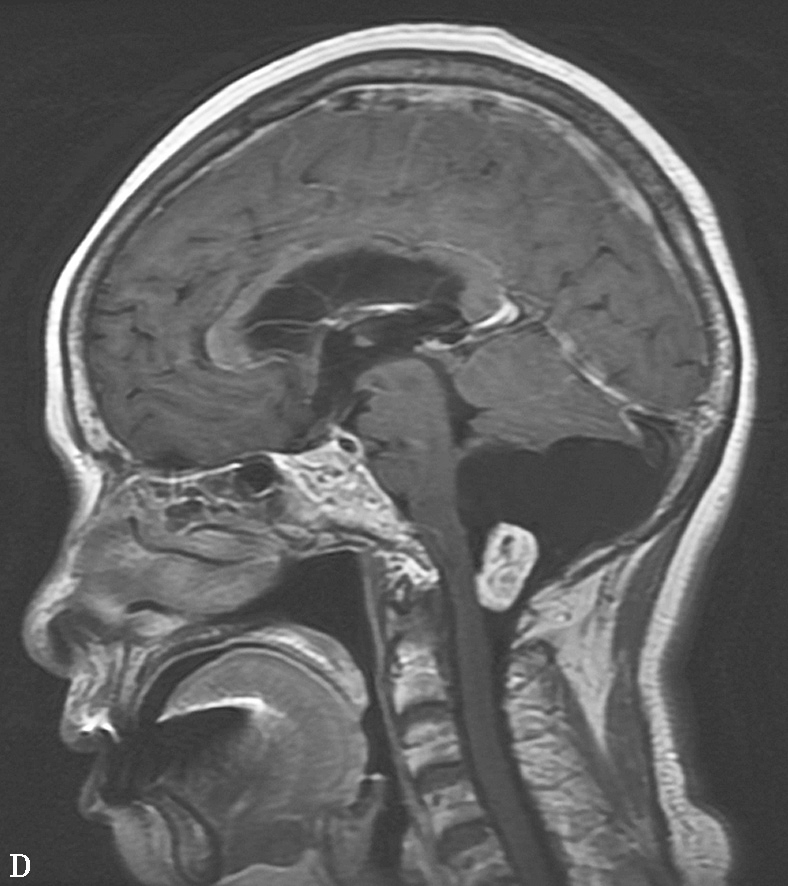

图1-12 血管母细胞瘤

图1-12 血管母细胞瘤(续)

C.T 2 WI矢状位;D.T 1 WI增强,示小脑蚓部见一囊性肿块,其内囊液呈长T 1 、长T 2 液性信号,囊壁有卵圆形等信号结节,呈“大囊伴小附壁结节”表现,增强扫描壁结节显著强化,囊壁不强化